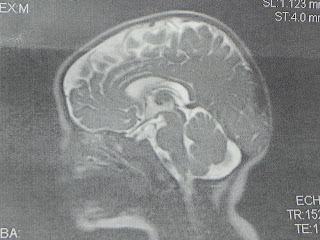

We got to the pediatric MRI area, where they had no record of us coming in today...they sent us to another area and these people were wonderful. They explained everything that was going to happen, asked me all kinds of questions and allowed me to ask whatever I wanted to. If you haven't ever had an MRI or haven't seen one, it is this huge round machine with a little tube that you slide into on a hard table. So what they did to PReston was have me lay him on the table with his head between two blocks and then they taped across his forehead to the blocks. They also rolled all kinds of blankets around his head and then put this cage like contraption over his head. I then inserted his little wubba nub in through the cage. They swaddled the rest of his body but then had me LAY ON TOP of him to help hold his chin in place! It was nuts! I am so thankful I wasn't claustraphobic because that would have been awful....And this is what we got today:

That is a picture of Preston's 100% NORMAL head and brain!!! I am rejoicing tonight in God's goodness to my family and I. I am just so relieved and thankful that Preston is ok.